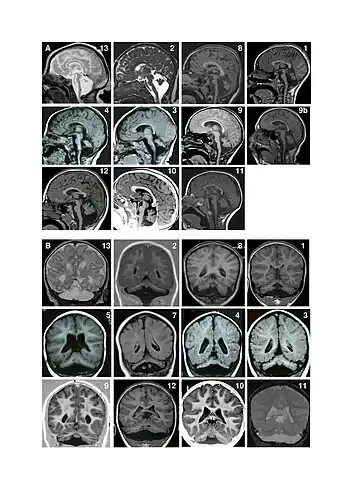

Magnetic resonance imaging (MRI) examples of patients with pontocerebellar hypoplasia with CASK mutations. A. Sagittal images showing different degrees of hypoplasia (incomplete formation) of the pons and vermis (parts of the brain). Numbers represent different patients. Figure 9a shows an MRI of a patient at age 4 months and figure 9b shows the same patient at age 11 years. There is no progression of the lesions between successive MRI in patient 9. Note that in all patients, the pons is very small but has a relative sparing of its bulging, mainly in its superior part. Hypoplasia predominates at the lower part of the pons. Vermis hypoplasia is very variable, severe in patient 13, very slight in patient 10-11-12 and also predominates at the inferior part. B. Coronal images showing varying degrees of cerebellar hemispheric (one of two halves of a part of the brain) hypoplasia. Hemispheres are frequently asymmetric. Note that the vermis does not protrude from the hemispheres indicating similar involvement of the vermis and the hemispheres. This pattern is different from that of PCH2 in which the vermis is relatively spared leading to the classic image of a "dragonfly", the protruding vermis being the body of the dragonfly and the hemispheres, the wings.